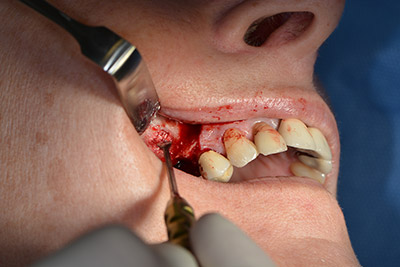

Procedura chirurgica per l'impianto

perforazione pilota

Immagine 9: panoramica e impostazione della perforazione pilota.

L'incisione classica (rilascio crestale e buccale) e la preparazione del lembo mucoperiosteo favoriscono un'ottima panoramica.

In questo caso vengono usati impianti di tipo SKY (bredent). Il loro protocollo chirurgico specifica una perforazione pilota di circa 1200 rpm (fig. 9).

Le vie indicate di seguito sono realizzate con una perforazione a velocità ridotta, pari a 300 rpm. In questa fase Implantmed dimostra la sua grande affidabilità. È possibile predefinire il protocollo chirurgico: per selezionare le varie posizioni, basta premere la lettera “P” con il controllo a pedale (da fig. 10 a 11).

Perforazione inclinata

Immagine 10: perforazione inclinata a livello dorso-craniale con velocità pari a 300 rpm.

controllo a pedale Implantmed di W&H

Immagine 11: il protocollo chirurgico di Implantmed può essere selezionato semplicemente azionando il controllo a pedale.

Il passaggio successivo consiste nel posizionamento dell'impianto, che nel nostro studio prevede una potenza pari a 32 Ncm (fig. 12).

Posizionamento dell'impianto

Immagine 12: posizionamento dell'impianto con forza pari a 32 Ncm.

Quindi, abbiamo optato per il rialzo del pavimento sinusale con impianto simultaneo. Implantmed è preimpostato sulla prima posizione per quanto riguarda la fenestrazione buccale della parete del seno mascellare.

La fenestrazione è impostata su 35.000 rpm, mentre la mucosa nasale viene preparata in direzione craniale (da fig. 13 a 14).

preparazione della mucosa nasale

Immagine 13

Immagine 14

Dunque, l'impianto viene posizionato e l'osso ricostruito. In questo caso, considerate le dimensioni della regione di accrescimento, i microframmenti dell'osso autologo (raccolti con un'apposita cannula di aspirazione in seguito alla perforazione dell'impianto 16 e della fenestrazione 14) vengono combinati con dei materiali di riempimento dell'osso.

Una membrana riassorbibile viene usata come barriera in direzione buccale per contenere l'accrescimento. Infine, vengono applicate suture resistenti alla saliva (da fig. 15 a 19).